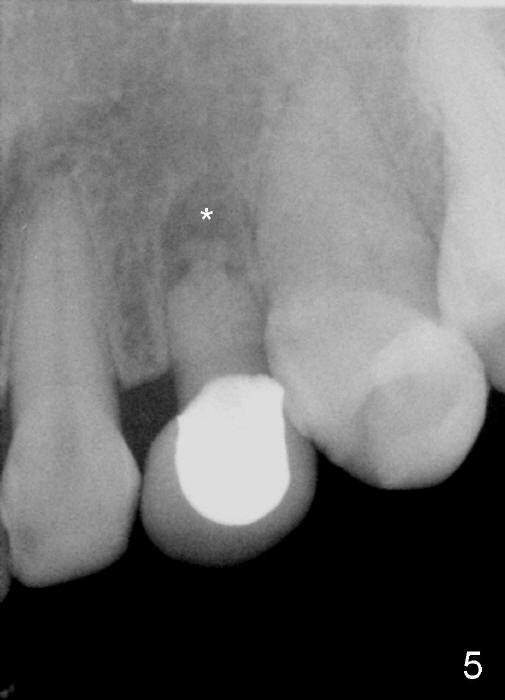

The upper left deciduous canine of a lady in her early forties looks functional 9 and 5 years ago (Fig.1,2). She wanted to close the diastema mesial to the deciduous tooth (Fig.2 *). The tooth was prepared for a provisional (Fig.3 P) and definitive restoration (Fig.4 C). The tooth becomes mobile 4 years post cementation (Fig.5).